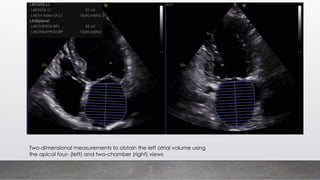

Two-dimensional measurements to obtain the left atrial volume using

the apical four- (left) and two-chamber (right) views